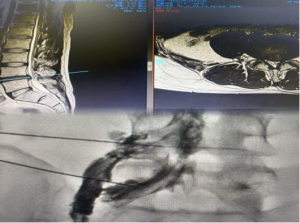

患者為31歲男性,因“腰椎間盤(pán)突出伴神經(jīng)根病”收入醫(yī)院脊柱外科。影像學(xué)檢查明確提示腰4/5椎間盤(pán)左后方突出,壓迫神經(jīng)根,導(dǎo)致劇烈腰腿疼痛,嚴(yán)重影響生活質(zhì)量。因?yàn)榛颊呒韧邪籽〔∈罚幱谠煅杉?xì)胞移植后狀態(tài),白細(xì)胞長(zhǎng)期低于正常水平,機(jī)體免疫防御能力極度脆弱。若實(shí)施常規(guī)的椎間孔鏡等有創(chuàng)手術(shù),圍手術(shù)期感染風(fēng)險(xiǎn)極高。

2025年12月15日,在完善的術(shù)前準(zhǔn)備和精確的影像引導(dǎo)下,疼痛診療科團(tuán)隊(duì)順利為患者實(shí)施上述聯(lián)合手術(shù)。手術(shù)過(guò)程順利,患者耐受良好。術(shù)后,患者之前難以忍受的腰腿痛癥狀得到明顯減輕。經(jīng)過(guò)短期觀察與康復(fù),患者疼痛控制滿意后出院。

術(shù)前腰椎MRI及術(shù)中圖片